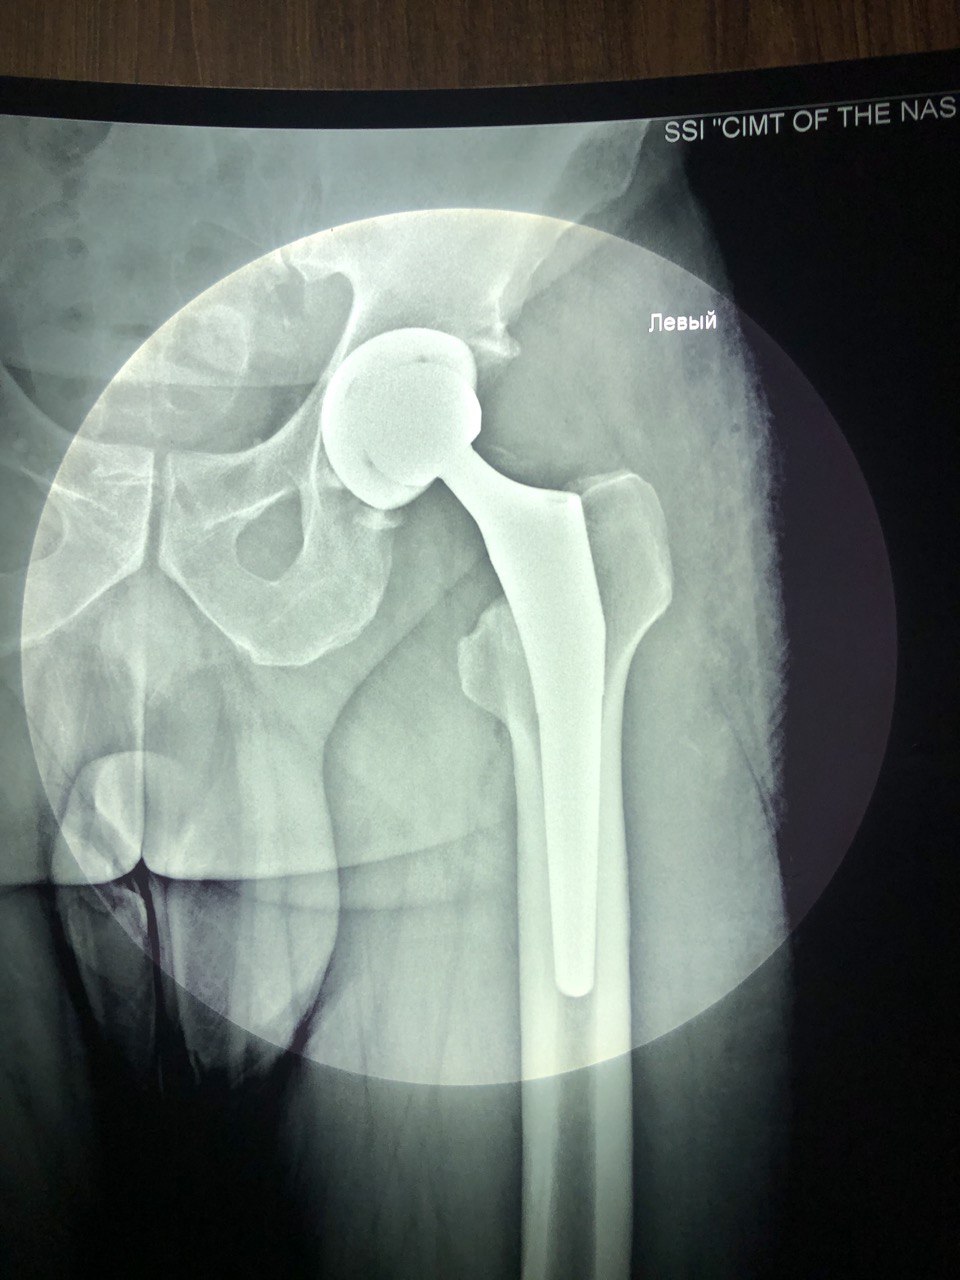

Діагноз: перелом основи шийки лівої стегнової кістки.

Було прийняте рішення про оперативне лікування: ендопротезування лівого кульшового суглоба.

1 фото- рентгенографія до операції.

2 фото- ренгенографія після операції.